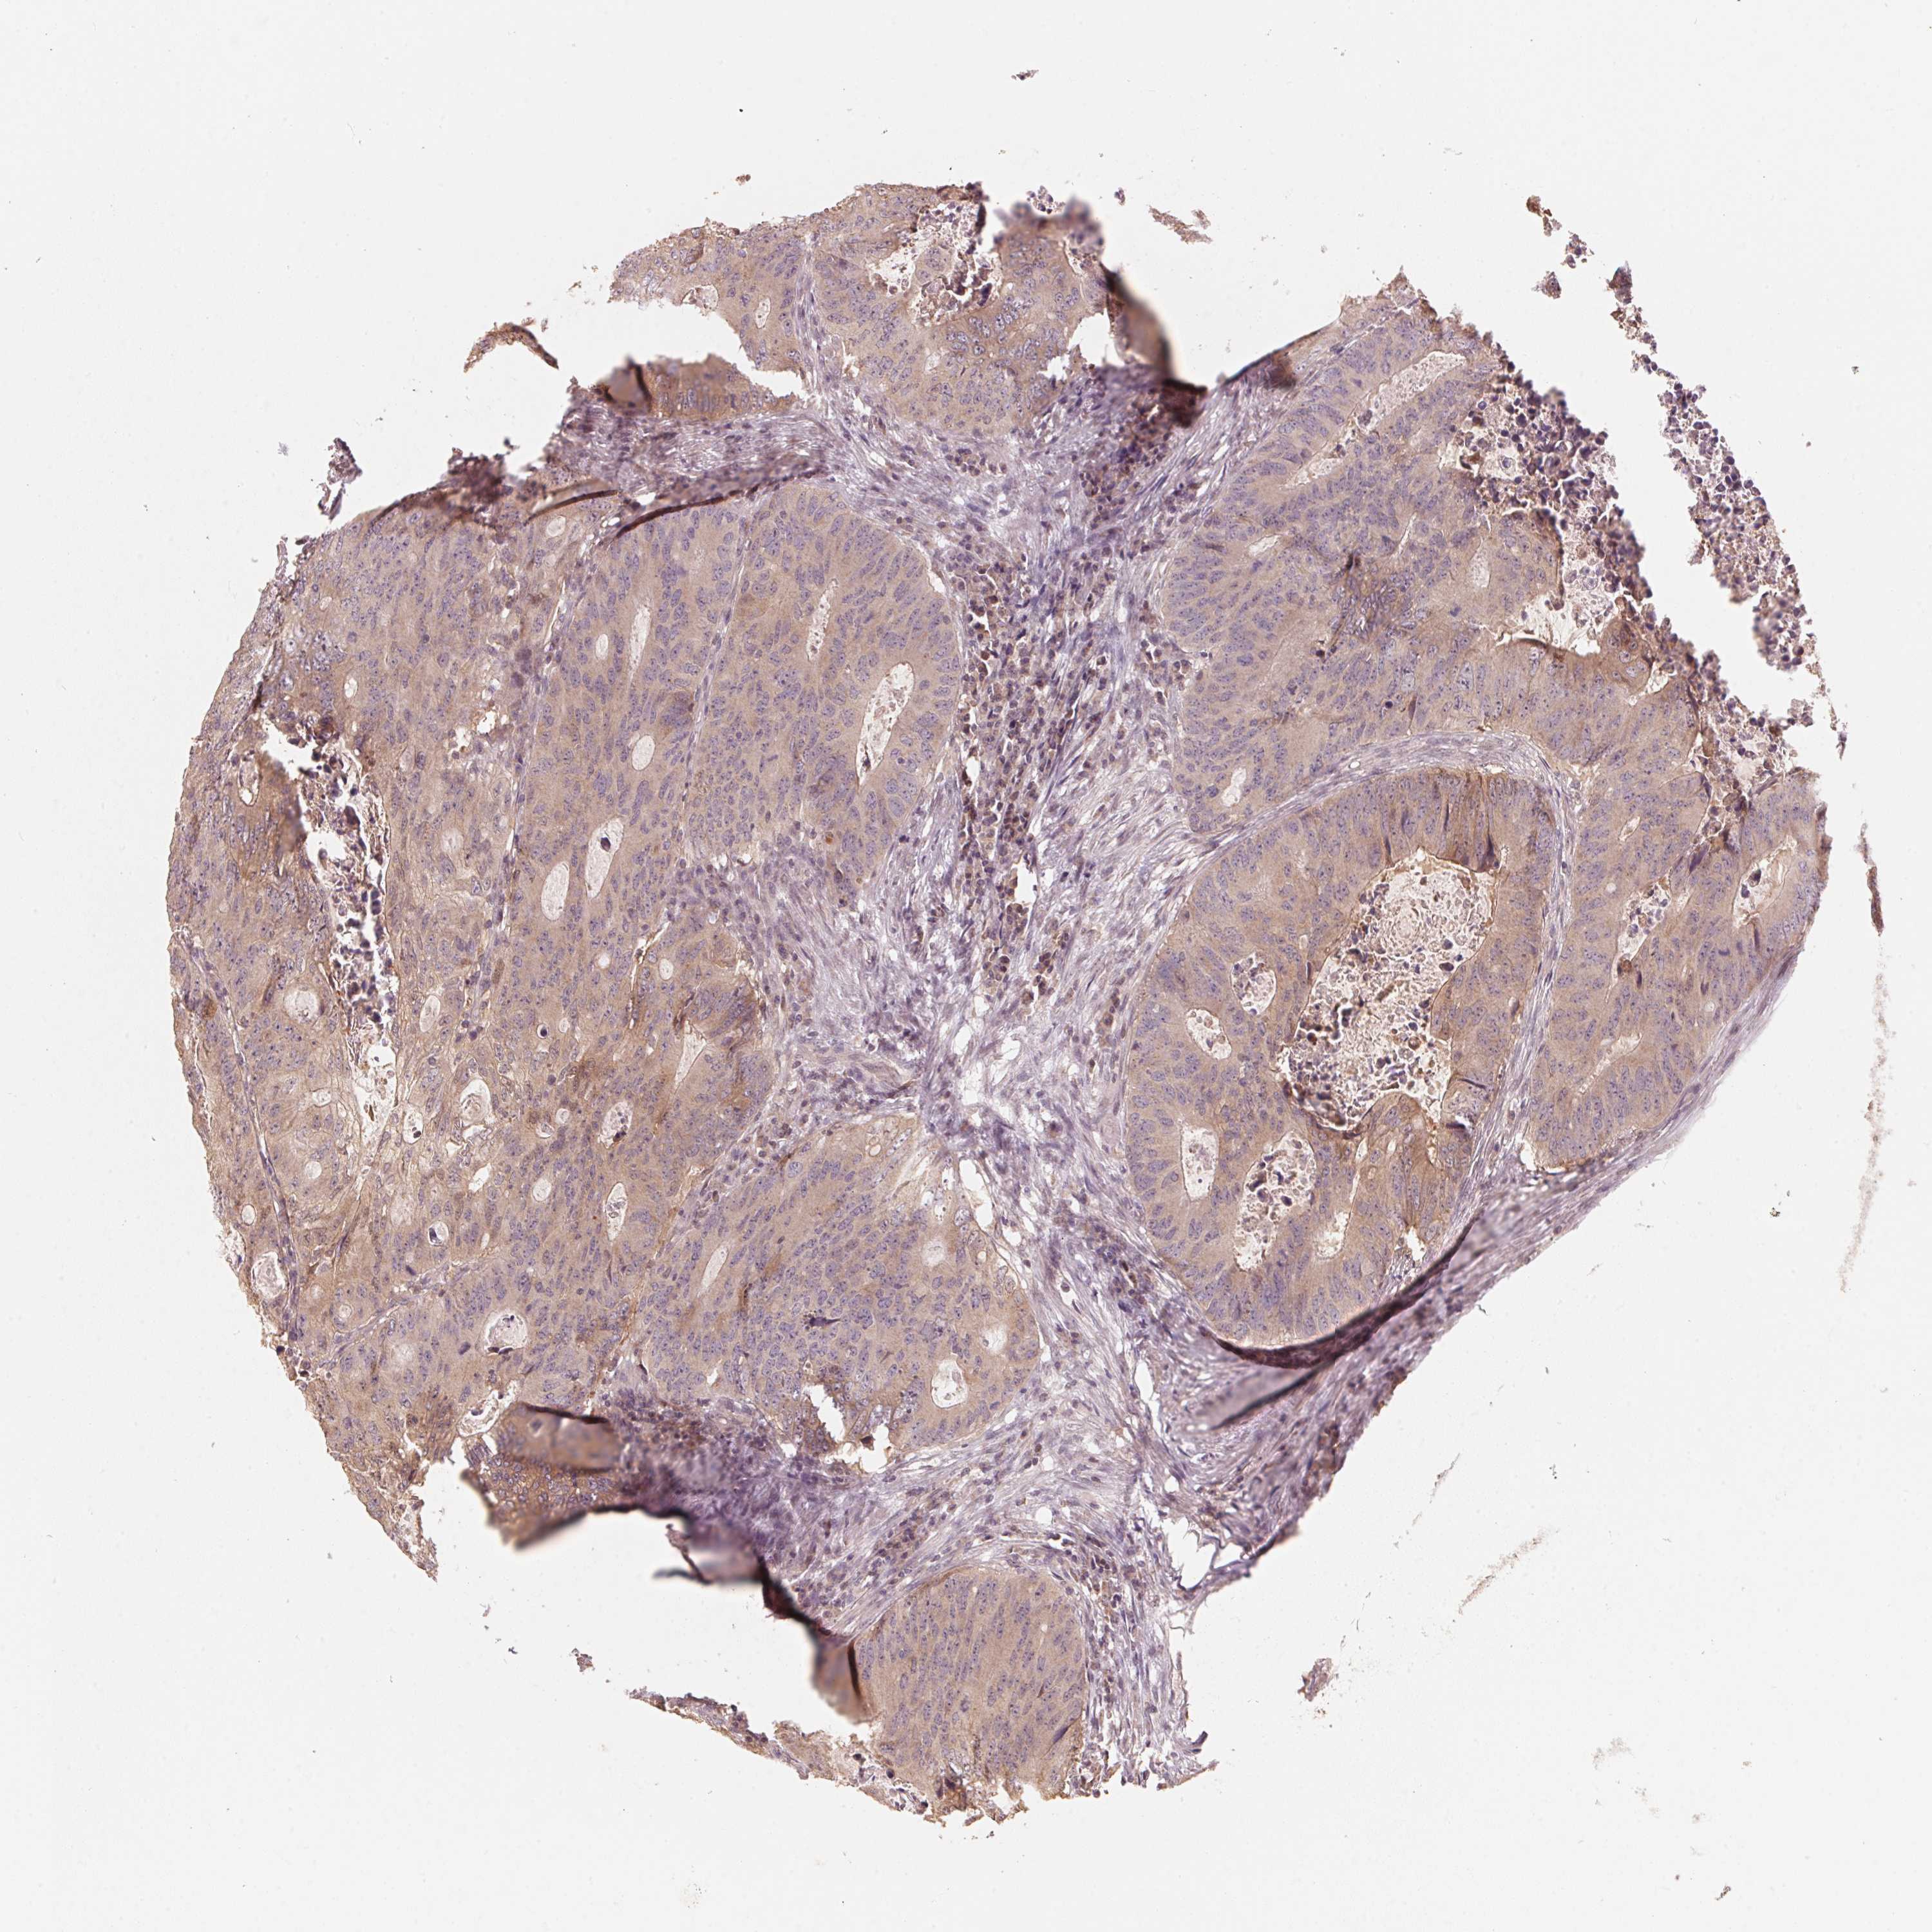

Colorectal cancer

Colon adenocarcinoma